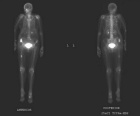

82 year old female with progressive right hip pain and no episodes of trauma.

Zoom image: Radiological image Radiological image.